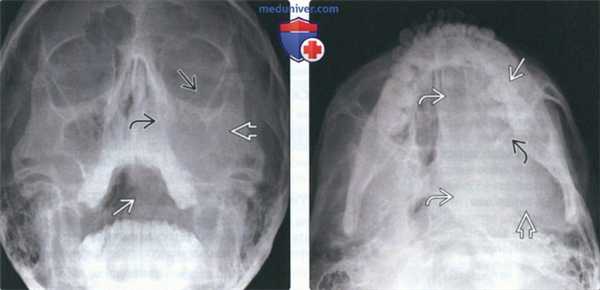

(Слева) На рентгенограмме в подбородочно-затылочной проекции в левой верхнечелюстной пазухе определяется неоднородное просветление, продолжающееся книзу к ротоглотке. Медиальная стенка левой верхнечелюстной пазухи неразличима, дно пазухи приподнято.

(Справа) На аксиальной рентгенограмме у этого же пациента определяется просветление в проекции левой верхнечелюстной пазухи полости носа, глотки, основания черепа слева. Задняя стенка верхнечелюстной пазухи четко не визуализируется.2. Рентгенография при саркоме Юинга челюсти: